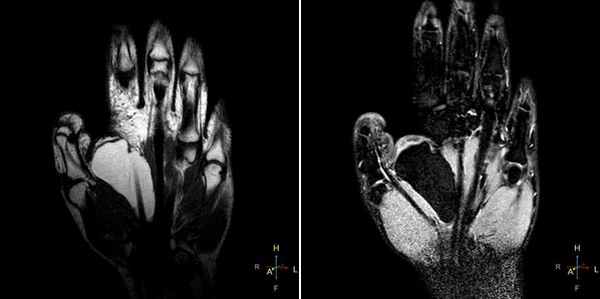

(Слева) МР-артрография в режиме Т1ВИ, коронарный срез: визуализируется крупный дефект ЛПС. Суставная щель расширена. Следует отметить наличиедегенеративных перфораций в центральной части ТФХК.

(Справа) МР-артрография в режиме Т2ВИ FS, коронарный срез: визуализируется крупный дефект ЛПС. Суставная щель расширена. Следует отметить неравномерное истончение хряща и кистозные изменения суставных поверхностей, обусловленные нестабильностью. Это говорит о том, что разрыв данной связки был биомеханически значим. (Слева) Артрография в заднепередней проекции: распространение контрастного препарата через дефект ЛПС в среднезапястный сустав. ПТС интактна.

(Справа) МР-артрография в режиме Т1ВИ, коронарный срез, этот же пациент: визуализируется интактный тыльный пучок ЛПС. Разрыв мембранозной порции на данном срезе не виден (располагается кпереди). Разрыв центральной мембранозной порции ЛПС часто протекает бессимптомно. (Слева) Непрямая МР-артрография в режиме Т1ВИ FS с КУ, коронарный срез: визуализируется значительное расширение ладьевидно-полулунного промежутка. Отмечаются признаки артрита лучеладьевидного сустава. Головчатая кость смещена проксимально в промежуток между ладьевидной и полулунной костями. Картина характерна для ПЛПК запястья.

(Справа) МР-артрография в режиме PD FS, сагиттальный срез, этот же пациент: определяется разрыв восстановленного фрагмента связки, имеющего аморфную структуру и неровный контур. Полулунная кость отклонена в тыльную сторону, что позволяет заподозрить ТНПС. Положение полулунной кости должно быть сопоставлено с осью ладьевидной кости на соседних срезах.